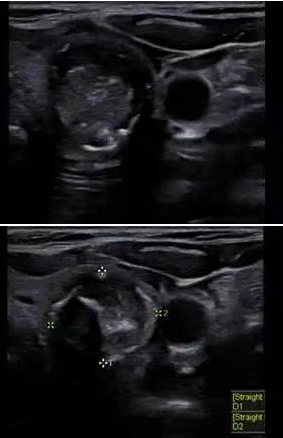

(3)纵切图像及彩色多普勒图像 二、(1)位患者结节的横向图像:有边缘样但不连续的钙化

(2)结节的纵向图像

(3)甲状腺其余部分正常

考虑良性还是恶性,是否需要进行活检?结果可能如何?你怎么认为? 简单分析下: 形:片状或地图样低回声,边界模糊 位:单侧或局部,其余实质回声正常 血:血流不增多,偶见稀疏点状